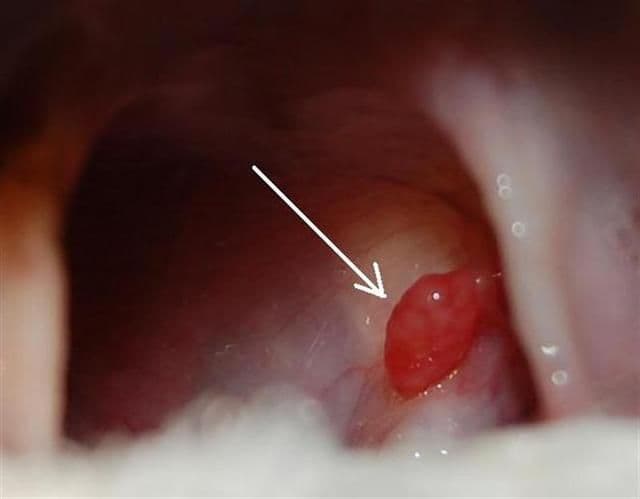

#betegség#garat#gyulladás#kutyaA garat és a mandulák betegségei@pbertold•2011. szept. 11.•1 perc olvasás